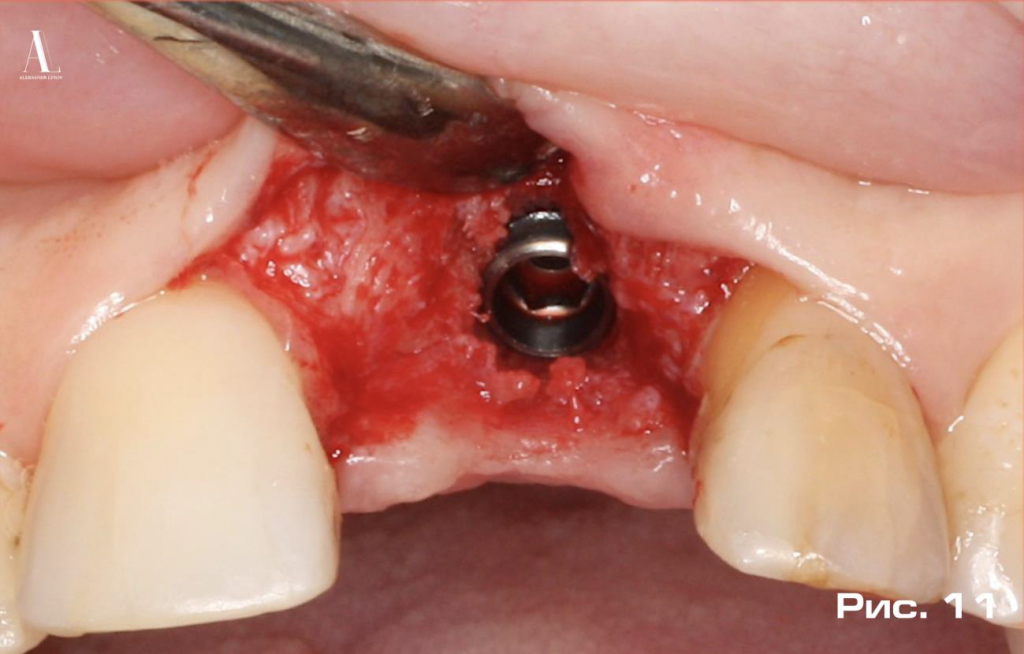

На рисунке 11 изображен имплантат, установленный в строго запланированном положении.